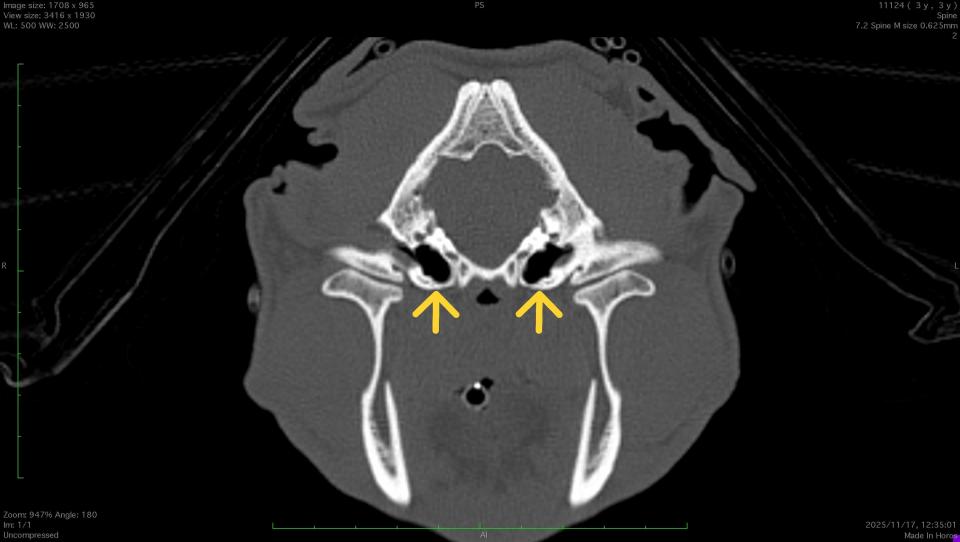

CT検査では、正常な鼓室胞は空気で満たされているので左画像のように黒く映ります。

一方、本症例では液体や軟部組織で鼓室胞内が満たされていることがわかります。